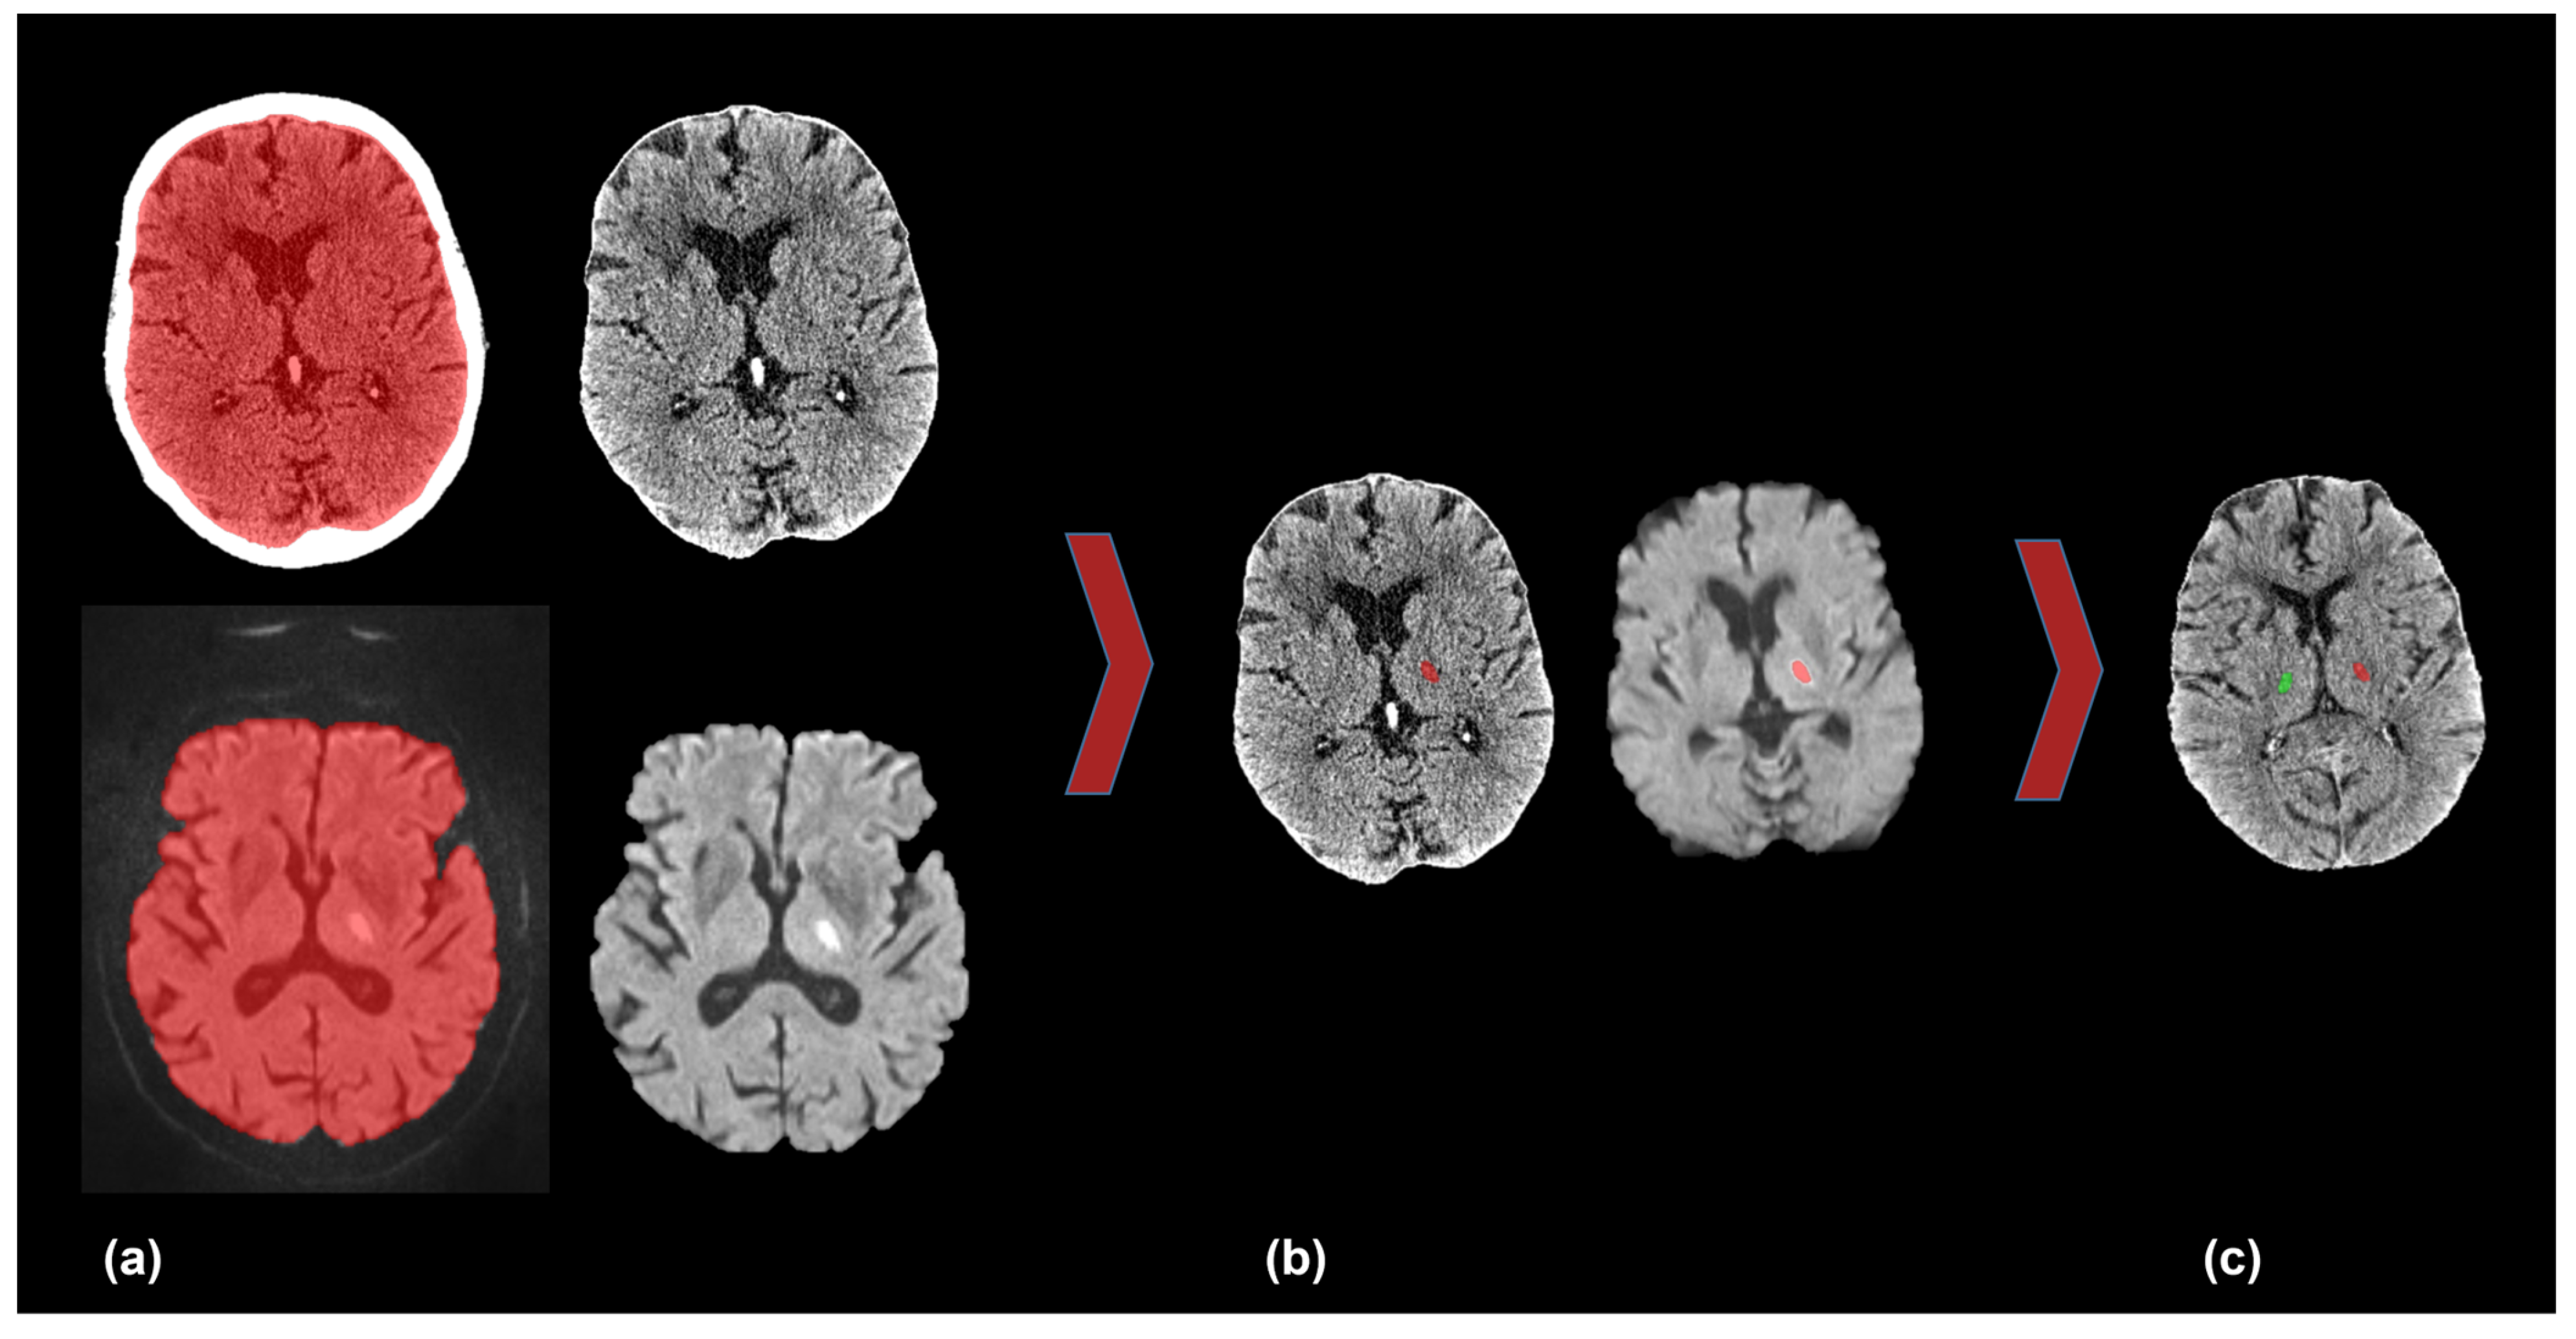

To quantify CT attenuation values of thalamic RSSI, a semi-automatic workflow of brain extraction, co-registration, and segmentation was performed. The aim was to mirror the infarcted area on DW-MRI to the NCCT to collect the CT attenuation values of the infarct and contralateral unaffected thalamus. Figure 1 illustrates the described workflow.

Figure 1.

Co-registration of DW-MRI and NCCT. (a) Semi-automatic segmentation and brain extraction in NCCT (upper row) and DW-MRI (lower row). (b) Co-registration of NCCT and DW-MRI and infarcted area in the left thalamus (red). (c) Mirroring the left-sided infarct (red) onto the unaffected contralateral right thalamus (green). DW-MRI = diffusion-weighted magnetic resonance imaging, NCCT = non-contrast computed tomography.

In detail, we exported the NCCT and DW-MRI data to the open-source software ITK-SNAP [20] and performed a threshold-based semi-automatic segmentation of the brain parenchyma followed by co-registration of the NCCT and MRI. Subsequently, we performed semi-automatic segmentation of the infarcted area in the DW-MRI, including the use of “binary erosion” and “fill hole” methods for image postprocessing. The areas of the DW-MRI lesion were shrunk by approximately 10%. We checked and manually corrected all segmentations if necessary. Then, we normalized and transferred the co-registered image data to the MNI 152 space [21,22]. Subsequently, we mirrored the segmentation of the infarcted area to the contralateral thalamus against the midline with the use of an in-house algorithm, again followed by visual verification. Finally, we transformed the mirrored segmentation back to the native NCCT space.